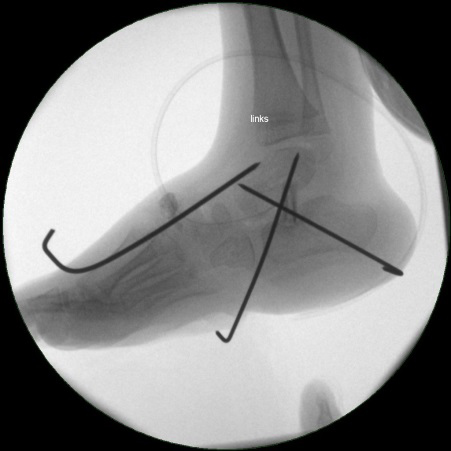

• Röntgenkontrolle (Bild 21,22).

• Im dargestellten Fall war zusätzlich eine plantarflektierende Cuneiforme mediale Osteotomie mit resorbierbarem Knochenersatz und eine Wadenmuskeldissektion nach Vulpius durchgeführt worden.